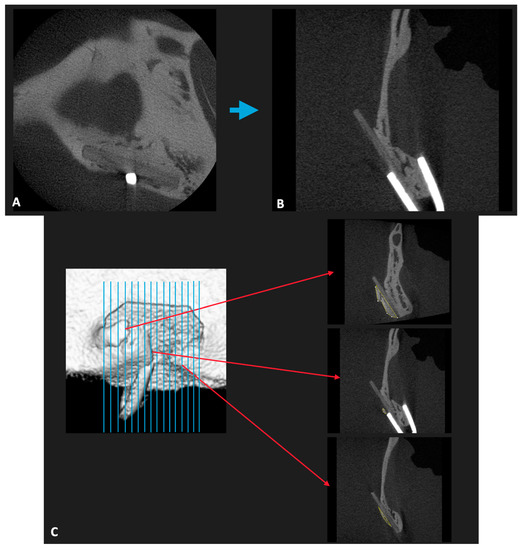

2.3. Evaluation of New Bone Formation in the Buccal Side via Micro-Computed Tomography (CT) in the Material Groups

3.1. Micro-CT Evaluation